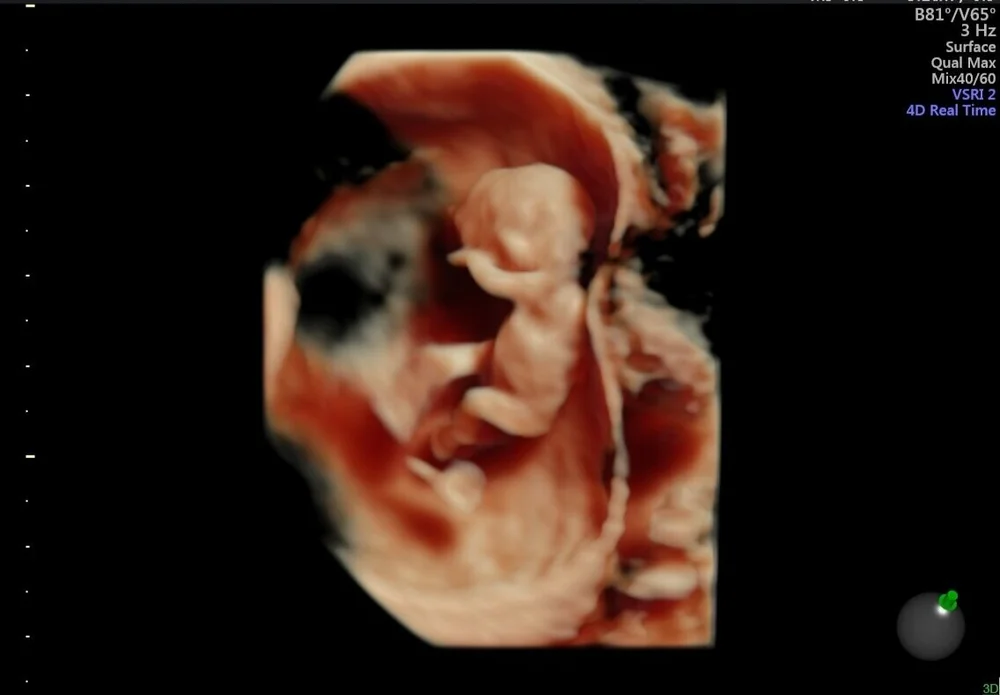

Seu bebê agora conhecido como feto está parecendo cada vez menos uma bolha rosa agora que a cauda desapareceuCom o tronco esticado e alongado seu pequeno tem aproximadamente 25 cm de tamanho nesta semana. Se suspeita que possa estar grávida está na altura de fazer um teste de gravidez que pode comprar na farmácia. 9 semanas de gestação e o desenvolvimento fetal.

No final desta semana seu feto terá cerca de 23 centímetros de comprimento e apenas 2 gramas de peso. Comprimento do embrião 25 cm medida da cabeça.